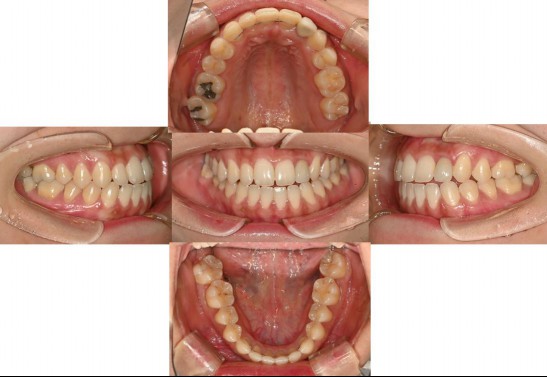

Dentists around the world must recognize that treating patients based on the conventional habitual jaw position can significantly impact their lives.

Not long ago, a practicing physician from Prague visited my clinic during orthodontic bracket treatment. She was diagnosed with facial asymmetry and body misalignment, and experienced MCB splint therapy. She was aware that bodily misalignment is related to asymmetry in the facial bones.

Yesterday, a person from Canada came in; this individual had undergone extraction orthodontics and whom I had consulted with online three years ago.